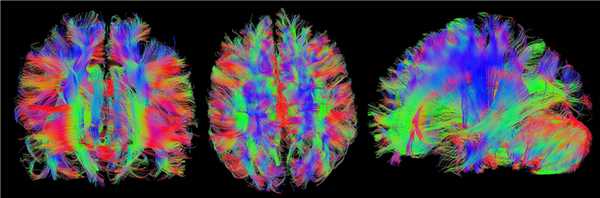

Нейрорадиологические особенности

Признак летучей мыши

На сагиттальных срезах почти всегда отмечается отсутствие червя мозжечка, хотя верхняя его часть (разделенная срединной расщелиной) в ряде случаев присутствует. Своеобразная парциальная гипогенезия червя приводит к появлению специфических формообразующих феноменов IV желудочка: его нижняя часть приобретает треугольноподобную форму, а верхняя благодаря частичной сохранности расщепленного червя — форму «летучей мыши». В нижних отделах задней черепной ямки — ниже гипопластичного червя церебеллярные гемисферы примыкают друг к другу по срединной линии. Верхние мозжечковые ножки не пересекаются в задних отделах среднего мозга и могут быть легко идентифицированы на фоне окружающей их спинномозговой жидкости, будучи позиционированы между средним мозгом и мозжечком. Мост уменьшен в переднезаднем размере (возможно, ввиду отсутствия перекреста пирамид).